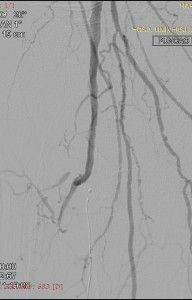

Paciente com diabetes tipo II e necrose isquêmica no segundo dedo do pé direito. Submetida a angiografia que evidenciou oclusão completa das artérias Tibiais e oclusão do Tronco Tíbio-fibular e segmento proximal da Fibular conforme as imagens abaixo.

Realizamos tentativa, sem sucesso, de recanalização do Tronco e da Fibular por via convencional (anterógrada).

Assim, planejamos nova abordagem por via retrógrada puncionando diretamente a artéria Fibular no terço distal com a paciente em decúbito dorsal. Tal punção foi realizada utilizando-se somente a agulha metálica do Jelco 18F.